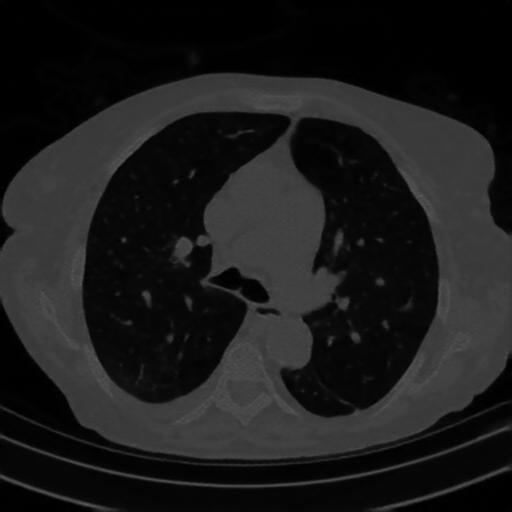

Original VENOUS CT scan

Full window (WL 1023.5, WW 4095 β†’ Low βˆ’1024, High +3071)

Lung window (WL -600, WW 1500 β†’ Low βˆ’1350, High +150)

Mediastinum window (WL 40, WW 400 β†’ Low βˆ’160, High +240)